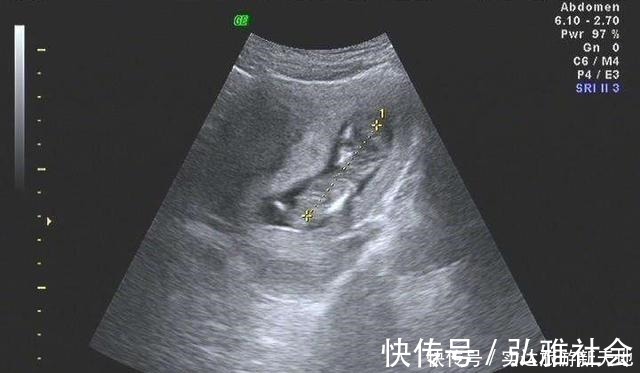

1、宝宝头臀长孕早期宝宝一般大约有5厘米长,在子宫内都是身体蜷缩的姿态,想要测量宝宝的长度是比较难的。所以大家一般会选择测量宝宝的头臀长。头臀长是指宝宝头部最顶端到宝宝臀部最底端的距离。正常的头臀长标准数据如下:孕期2个月:(3.27cm至4.14cm)孕期3个月:(4.3cm至5.29cm)孕期4个月:(5.47cm至6.59cm)孕期5个月:(6.78cm至8.02cm)具体测量孕周方法的公式:孕周期=CRL+6.5,假如,B超数据单的头臂径是6.03厘米,那么宝宝的孕周期是6.03+6.5=12.53周。